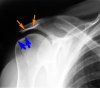

Импинджмент синдром плечевого сустава